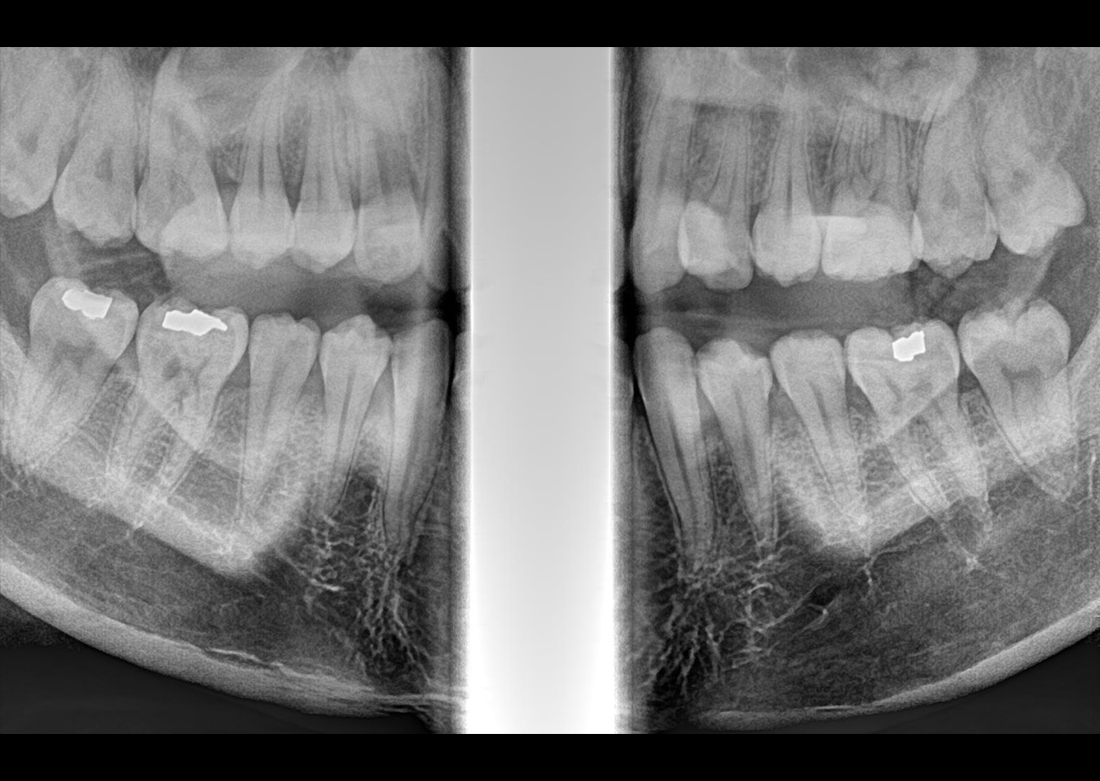

The Papaya 3D Premium/Ultra is the newest generation in a long line of Genoray products designed to produce accurate diagnostic images with wider treatment applications including implants, endo, ortho, airway, TMJ, and orthognathic surgeries. Optimized acquisition PC/Monitor/Accessories, model scan/STL converter, and perpetually licensed software suites included.

- Papaya 3D Premium CBCT: Min 4x5 to Max 16x14 FOV

- Papaya 3D Ultra CBCT: Min 4x5 to Max 23x24* FOV